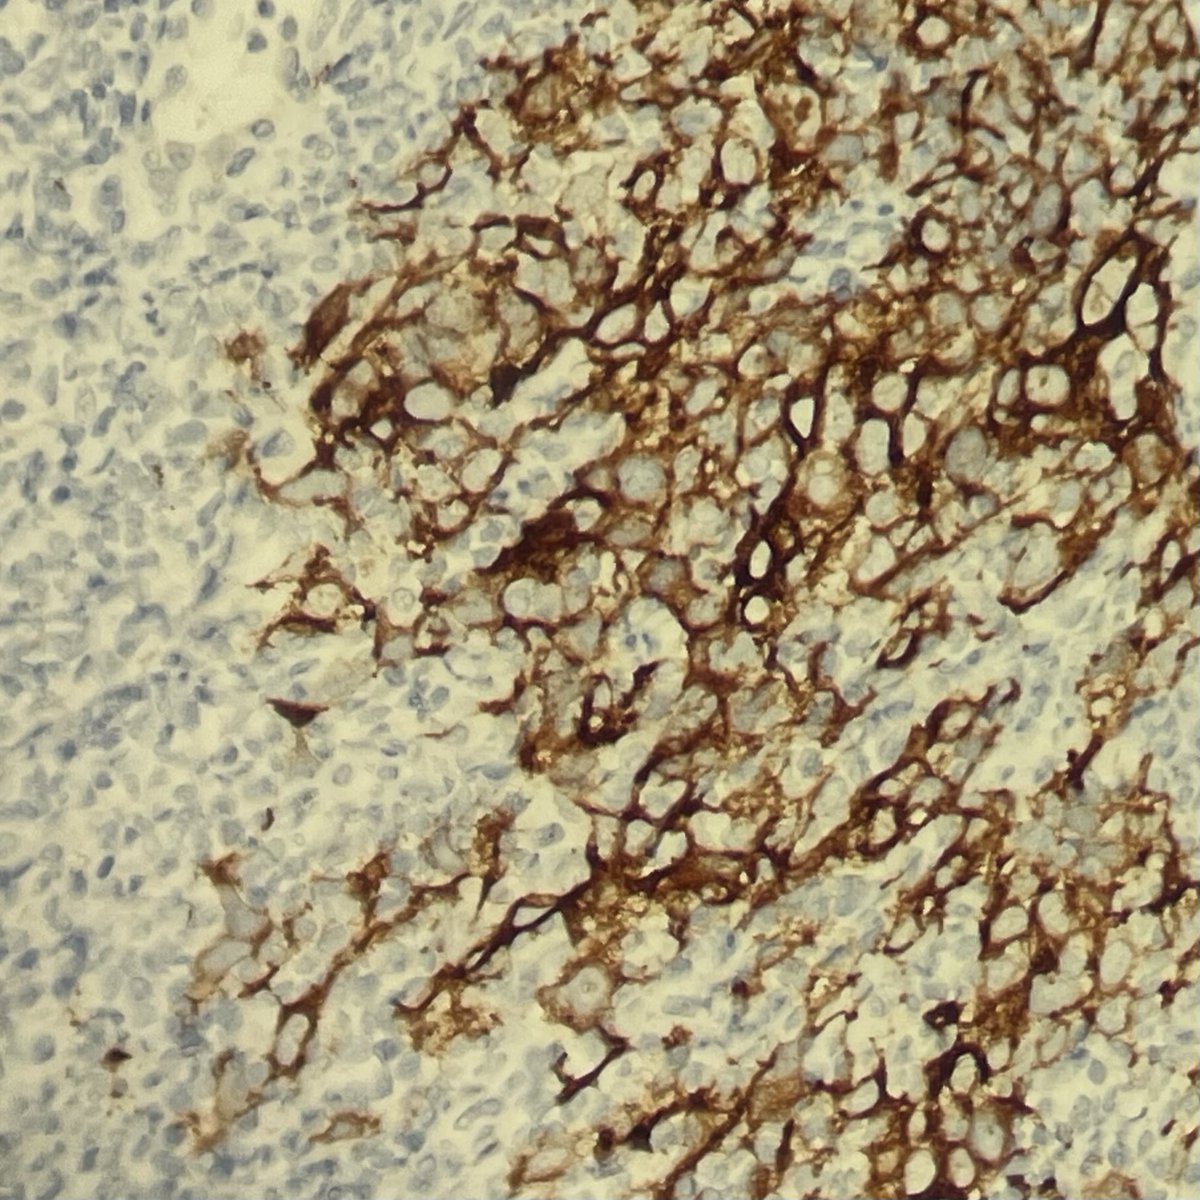

🔔 Answer Reveal! This myxoid mystery 🪼🔬 was… 🥁 Matrix-producing metaplastic carcinoma! 💥🦴 CAM5.2 shown below 👇. Note the markedly atypical focus with glandular differentiation and abruption transition to chondroid 👀 #PathQuiz #PathX #PathTwitter #breastpath